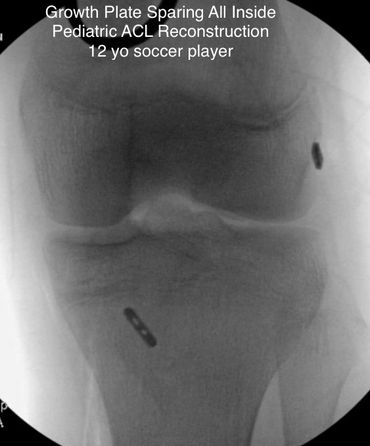

- Pediatric ACL Surgery